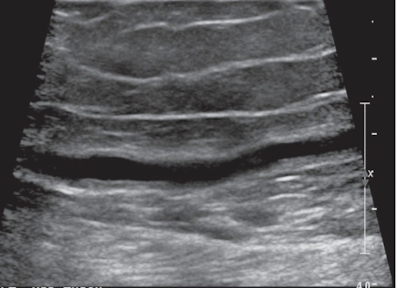

Normal walls of a INSITU vein graft should appear as…

smooth and uniform